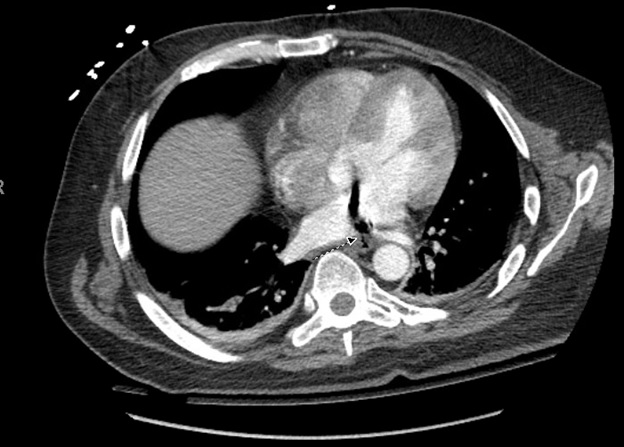

Case Presentation: We present a case of a 42-year-old male with a past medical history of atrial fibrilation (AF) on anti-coagulation (AC) who underwent left atrial radio-frequency ablation (RFA) and pulmonary vein isolation (PVI) and presented with confusion and bilateral upper and lower extremity weakness.The patient tolerated the procedure but complained of difficulty swallowing afterwards. Five days later, he began having malaise and GI upset which was associated with an episode of loose bright red blood bowel movement. He later became more confused, began to have weakness in all of his extremities, and was admitted to the hospital for workup. Imaging of the brain revealed multiple focal areas of subacute infarcts consistent with multiple embolic events involving the bilateral frontal lobes, left parietal and right temporal lobes. CT of the chest also revealed air next to the posterior wall of left atrium which was thought to be secondary to AEF as a complication of his RFA. His hospital course was complicated by seizure, sepsis secondary to aspiration pneumonia, and cardiac arrest requiring several rounds of chest compression. Immediately after he regained pulse, he was noted to be posturing with worse mental status, and a CT of the head showed multiple air emboli bilaterally with a higher stroke burden when compared to his initial CT scan. The patient was deemed non-operable, and was eventually discharged to long term acute care facility.